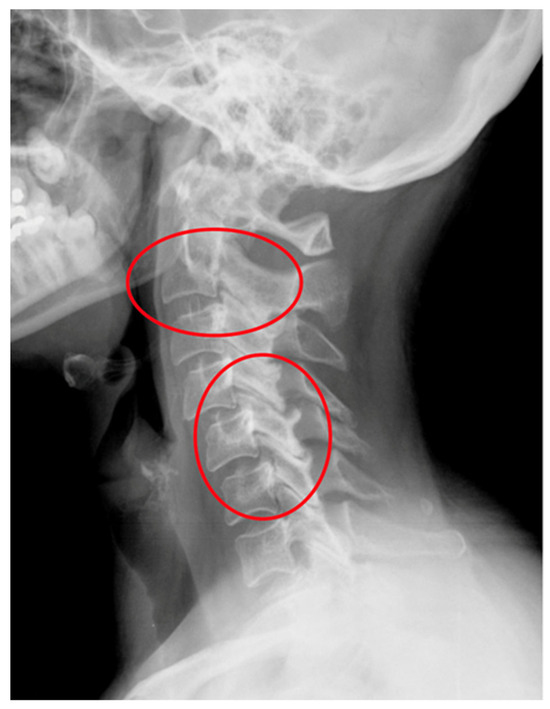

| AAS (atlantoaxial subluxation) | Weakening or rupture of ligaments and subchondral bone erosion in the atlantoaxial C1–C2 joints. |

| SAS (subaxial subluxation) | Subluxation in the joints C2–C7 due to destruction of the joint surface and the ligaments between the processes spinosis. |

| CS (cranial settling) | Vertical translocation of dens C0–C2 into the foramen magnum. |